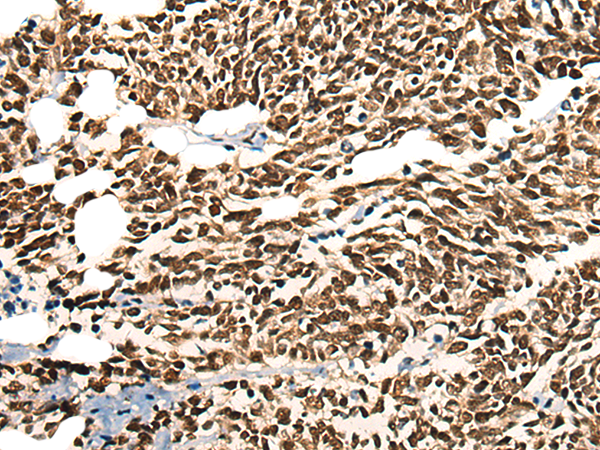

IHC positive control: |

Human gastric cancer |

IHC Recommend dilution: |

25-100 |